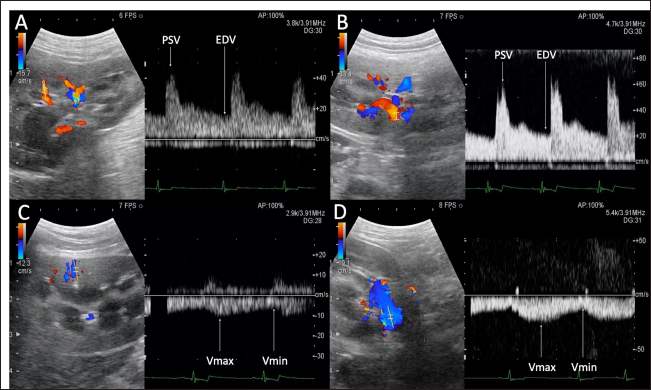

Fig. 1. Renal blood flow waveform on pulsed Doppler ultrasonography. Flow waveform of the renal interlobar artery (A), renal artery (B), renal interlobar vein (C), and renal vein (D). The arterial blood flow waveform peaks sharply and quickly during systole (PSV), after which the flow velocity gradually slows to a minimum at end-diastole (EDV). The venous blood flow waveform is continuous, with the fastest waveform (Vmax), followed by a gradual slowing to a minimum (Vmin). EDV, end-diastolic velocity; PSV, peak systolic velocity; Vmax, maximum venous flow velocity; Vmin, minimum venous flow velocity. One-way random-effects intraclass correlation (ICC1,3) was used to assess the intraobserver agreement of each measurement. The level of reliability was defined as poor (ICC < 0.5), moderate (0.5 < ICC < 0.75), good (0.75 < ICC < 0.9), or excellent (ICC > 0.9) for intraobserver reliability (Koo and Li, 2016). For such analysis, commercial statistical software (BellCurve for Excel, Social Survey Research Information, Tokyo, Japan) was used, and p-values < 0.05 were considered as statistically significant. Ethical approvalThis pilot study was prospectively designed in accordance with the replacement, reduction, and refinement (3R) principle and was approved by the Rakuno Gakuen Animal Experiment Committee (approval number: VH18B9). ResultsThe median age of the 10 dogs was 5 years (range: 4–8 years), and the median weight was 11.2 kg (range: 9.2–14.2 kg). In the current study, there was no opportunity to use parametric tests when comparing the two items because either both were not normally distributed or only one had a normal distribution. Therefore, only nonparametric tests were used in this study. Before and after sedation, the median systolic blood pressure was 144.5 mmHg (range: 128–160 mmHg) and 122.5 mmHg (range: 101–159 mmHg), the median diastolic blood pressure was 77.0 mmHg (range: 68–112 mmHg) and 66.0 mmHg (range: 56–86 mmHg), and the median and mean blood pressure were 99.5 mmHg (range: 79–133 mmHg) and 85.0 mmHg (range: 68–100 mmHg), respectively. With no sedation, one patient had a systolic blood pressure of 160 mmHg. However, under sedation, all patients had a systolic blood pressure of less than 160 mmHg. In addition, significant reductions in systolic, diastolic, and mean blood pressure were observed after sedation (p=0.04, 0.04, and 0.03, respectively). The median GFR was 5.65 ml/minute/kg (range: 2.2–7.8 ml/minute/kg), while the renal functional reserve was 81.5% in one case and >100% in the remaining nine cases. There were no significant correlations between the GFR and renal function markers (Table 1). The renal vein blood flow waveform showed a continuous pattern in all cases. The Vmax (r=−0.67 and p=0.04) and Vmin (r=−0.79 and p=0.01) of the left renal vein showed a significant negative correlation with body-weight-standardized GFR. Similarly, Vmax (r=−0.76 and p=0.02) and Vmin (r=−0.75 and p=0.02) of the right renal vein also displayed a significantly negative correlation with GFR (Table 1 and Fig. 2). The VII of the renal veins; Vmin, Vmax, and VII of the renal interlobar veins; and the PI, RI, PSV, and EDV of the renal and renal interlobar arteries were not significantly correlated with GFR. No significant differences were observed between the left and right kidneys in the interlobar artery/vein or renal artery/vein (Table 1). Interlobar arterial/venous and renal arterial/venous measurements showed no significant differences between the left and right kidneys (p > 0.05). Also, no adverse events were observed in the study. The intraobserver reliabilities of PSV, PI, Vmax, and Vmin were good or excellent at all sites. Only the intraobserver reliability of VII for the left interlobular vein was poor (Table 2). DiscussionThe hypothesis of this study was that renal venous blood flow is closely related to GFR and that changes in the renal venous blood flow waveform are associated with a decrease in GFR, resulting in changes in Vmax, Vmin, and VII. Thus, Vmax and Vmin in the renal veins were negatively correlated with the GFR. In contrast, no change in the renal vein waveform was observed in the dogs. In addition, VII and renal venous flow velocity in the interlobar veins were not significantly correlated with GFR. Nijst et al. (2017) reported that discontinuous patterns were observed in approximately 80% of patients with heart failure and that the percentage decreased to approximately 30% with diuretic treatment. In contrast, they reported that no discontinuous pattern was observed in normal patients (Nijst et al., 2017). These results suggest that discontinuous patterns are seen in renal congestion associated with heart failure, and such discontinuous patterns are not observed in normal patients. In humans, renal venous flow evaluation using pulsed Doppler ultrasonography aids in the diagnosis of diabetic neuropathy, obstructive urinary tract disease, and pre-eclampsia (Bateman and Cuganesan, 2002; Bateman et al., 2004; Oktar et al., 2004; Jeong et al., 2011; Kudo et al., 2017). In diabetic nephropathy and obstructive urinary tract disease, VII is low (i.e., the change in Vmax is relatively decreased (Bateman and Cuganesan, 2002; Oktar et al., 2004; Jeong et al., 2011; Kudo et al., 2017), whereas in pre-eclampsia, VII is high [i.e., the change in Vmax is relatively increased (Bateman et al., 2004)]. In other words, a change in VII is accompanied by a change in the waveform. In a previous study, waveform changes were found to be caused by increases in downstream resistance, reductions in the pressure gradient between the renal veins and the right atrium, and increases in venous compliance (Bateman et al., 2004; Jeong et al., 2011). However, this study was based on normal dogs. Thus, VII may not have been affected because there were no pathological conditions among the patients in the current investigation that could have caused waveform changes. Table 1. Correlation between GFR, biomarkers, and ultrasonographic parameters.